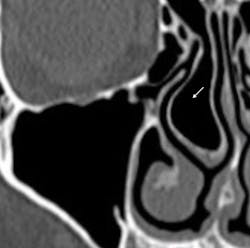

- Second, is there any infection risk because of postsurgical alteration of sinus physiology? There are a few local and systemic factors that may lead to postoperative infectious complications. The first factor is local anatomy and anything that alters the drainage pathways through the ostium. Sinus surgery that results in blockage of the ostium, particularly if the natural opening is thin, can lead to sinus infection (figure 5). The second factor is tooth-related preservation of infected teeth that drain into the sinus, which can contaminate the graft and lead to sinus graft infection postsurgery. The third factor is any systemic disease that lowers the body’s capability of fighting infection, which can result in sinus infection postsurgery. These infections can be minimized through careful review of medical history and appropriate case selection.

Figure 5: The sinus ostium is narrow because of the concha bullosa (arrow).